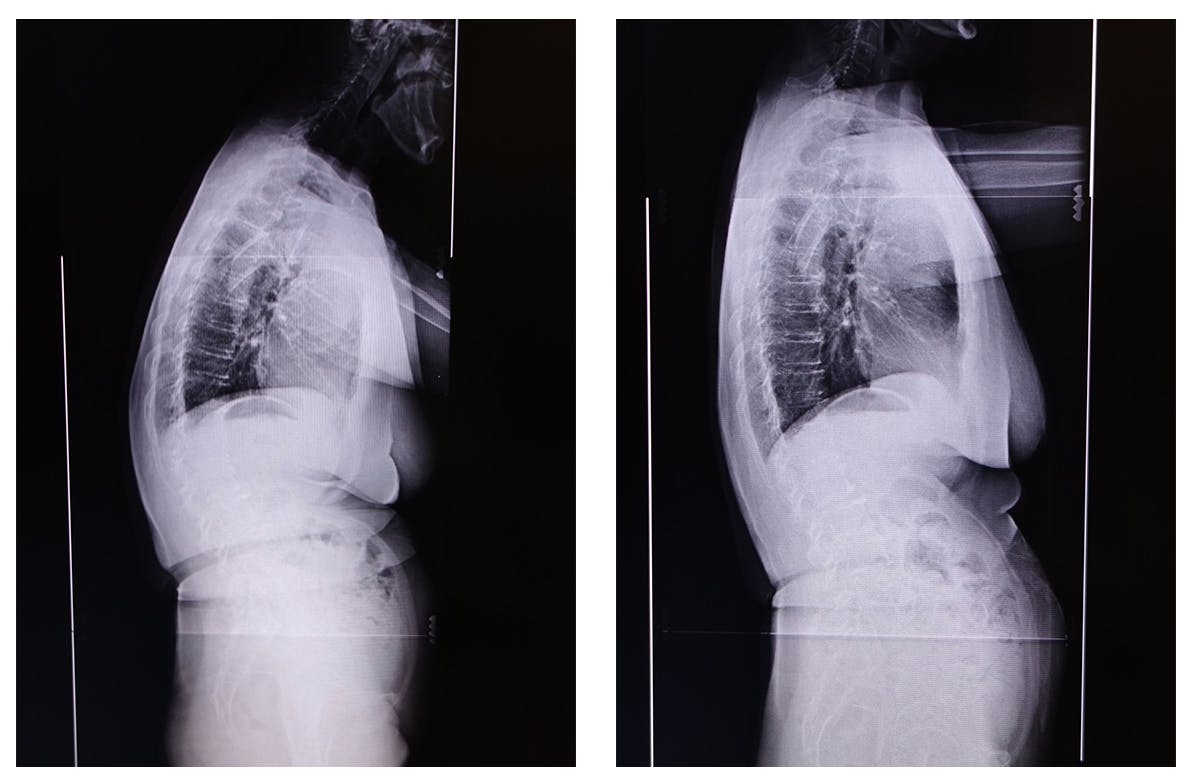

人類の祖先は、チンパンジーやゴリラと同じように四足歩行で両手を地面につけながら移動し、腰椎もまっすぐでした。しかし、人間は両手を使うために二足歩行に進化し、脳の発達と知識の獲得に伴い、脳は肥大化しました。その結果、歩行時の脳への衝撃を緩和するために、腰椎はS字カーブ(ダブルS字)の形状に進化したとされています。

座る姿勢を長時間維持すると、最初は正しい姿勢で背筋を伸ばしていても、徐々に疲れが蓄積し、腰椎のS字カーブが崩れてしまうため、避けられないことです。

この結果、腰椎に存在する椎間板が変形し、神経を圧迫して腰痛の原因となります。したがって、「座る姿勢」というのは、腰椎にとって過酷な状況になるメカニズムが存在するのです。